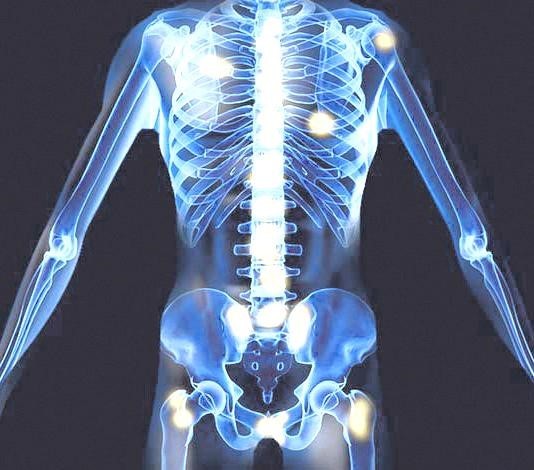

오늘은 남성의 건강을 지키는 중요한 기관, 전립선에 좋은 음식에 대해 이야기하려 합니다. 전립선은 방광 아래에 위치하며 정액을 구성하는 액체를 생산하는 기관입니다.

전립선에 좋은 음식 나이가 들면서 전립선 비대증이나 전립선암과 같은 질환에 노출될 위험이 커지므로, 평소 식단 관리를 통해 전립선 건강을 챙기는 것이 매우 중요합니다. 지금부터 전립선 건강을 지키는 10가지 효과적인 음식을 꼼꼼히 살펴보고, 건강을 위한 첫걸음을 함께 시작해 볼까요? 👨⚕️